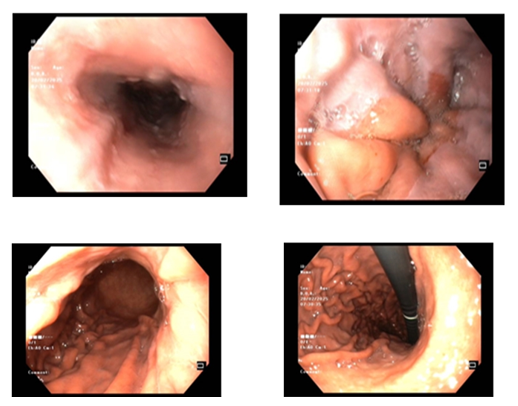

Ca lâm sàng: Ung thư đại tràng ở bệnh nhân 15 tuổi

GS.TS Mai Trọng Khoa; BSNT Hoàng Mạnh Đức, Ths Bùi Quang Lộc , PGS.TS Phạm Cẩm Phương, Bsck II Hoàng Anh, Trung tâm y học hạt nhân và...